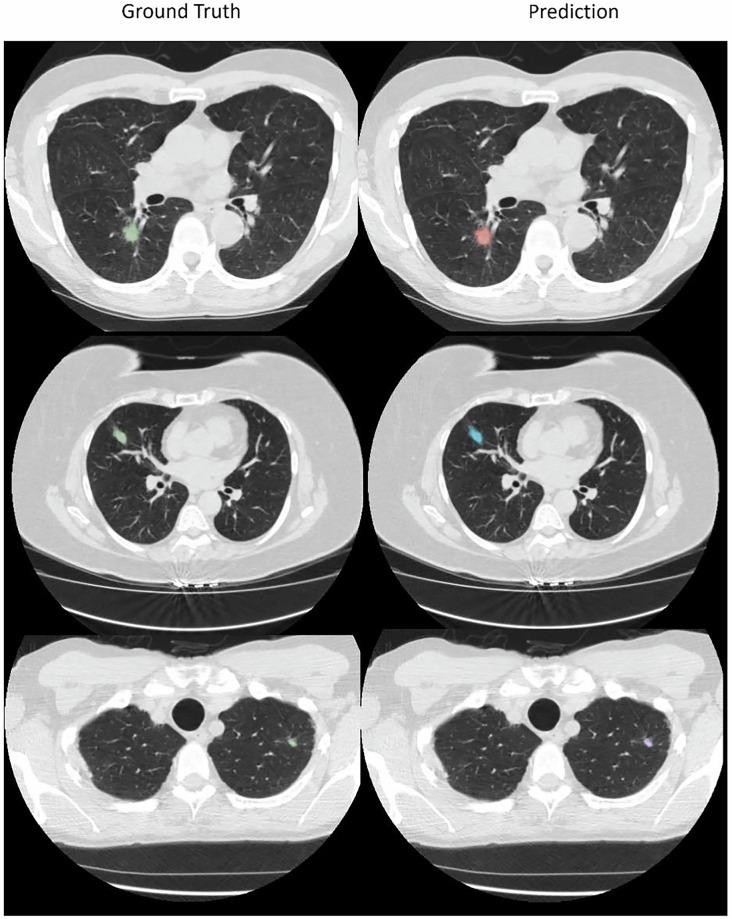

Low-dose computed tomography (LDCT) is the most effective tools for early detection of lung cancer. With advancements in artificial intelligence, various Computer-Aided Diagnosis (CAD) systems are now supported in clinical practice. For radiologists dealing with a huge volume of CT scans, CAD systems are helpful. However, the development of these systems depends on precisely annotated datasets, which are currently limited. Although several lung imaging datasets exist, there is only few of publicly available datasets with segmentation annotations on LDCT images. To address this problem, we developed a dataset based on NLST LDCT images with pixel-level annotations of lung lesions. The dataset includes LDCT scans from 605 patients and 715 annotated lesions, including 662 lung tumors and 53 lung nodules. Lesion volumes range from 0.03 cm to 372.21 cm, with 500 lesions smaller than 5 cm, mostly located in the right upper lung. A 2D U-Net model trained on the dataset achieved a 0.95 IoU on training dataset. This dataset enhances the diversity and usability of lung cancer annotation resources.

低剂量计算机断层扫描(LDCT)是早期检测肺癌最有效的工具。随着人工智能的发展,目前临床实践中支持各种计算机辅助诊断(CAD)系统。对于处理大量CT扫描的放射科医生来说,CAD系统很有帮助。然而,这些系统的开发依赖于精确标注的数据集,而目前此类数据集有限。尽管存在几个肺部影像数据集,但只有少数公开可用的LDCT图像分割标注数据集。为了解决这个问题,我们基于NLST LDCT图像开发了一个具有肺部病变像素级标注的数据集。该数据集包括来自605名患者的LDCT扫描和715个标注病变,其中包括662个肺肿瘤和53个肺结节。病变体积范围从0.03立方厘米到372.21立方厘米,500个病变小于5立方厘米,大多位于右上肺。在该数据集上训练的二维U-Net模型在训练数据集上实现了0.95的交并比。这个数据集增强了肺癌标注资源的多样性和可用性。